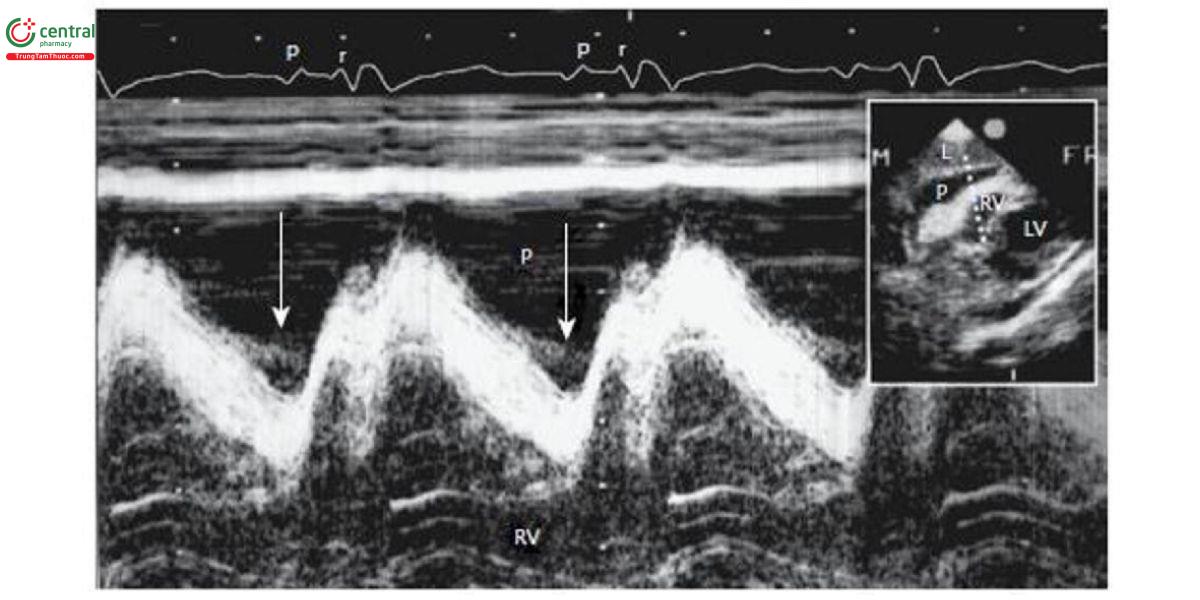

Chiếm tỉ lệ khoảng 20%, thường tiến triển, bóc tách chậm cơ tim, xuất huyết trong khoang màng ngoài tim được bít bởi màng ngoài tim hay huyết khối trong cơ tim (Hình 1B). Bệnh nhân có thể sống vài giờ cho đến khi xuất huyết ồ ạt. Biểu hiện là tụt huyết áp và tràn dịch màng tim. Siêu âm tim có thể thấy chèn ép nhĩ phải (Hình 2), thất phải (Hình 3), đảo ngược đường cong vách liên nhĩ. Tuy nhiên, đây là dấu hiệu gián tiếp có thể dương tính giả. Chọc rò màng ngoài tim có thể giúp chẩn đoán khi có máu trong màng tim nhưng cũng có thể dương tính giả do chạm thương hay do biển chứng rò động mạch vành (ĐMV) sau can thiệp ĐMV qua da.